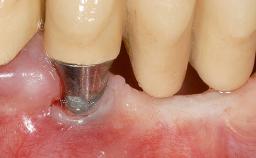

The patient, a healthy 38-year-old woman, was referred for increasing the width of the keratinized tissues at the buccal aspect of dental implant 46. The site exhibited a premature-closure screw exposure caused by trauma during chewing, with inadequate keratinized tissue.